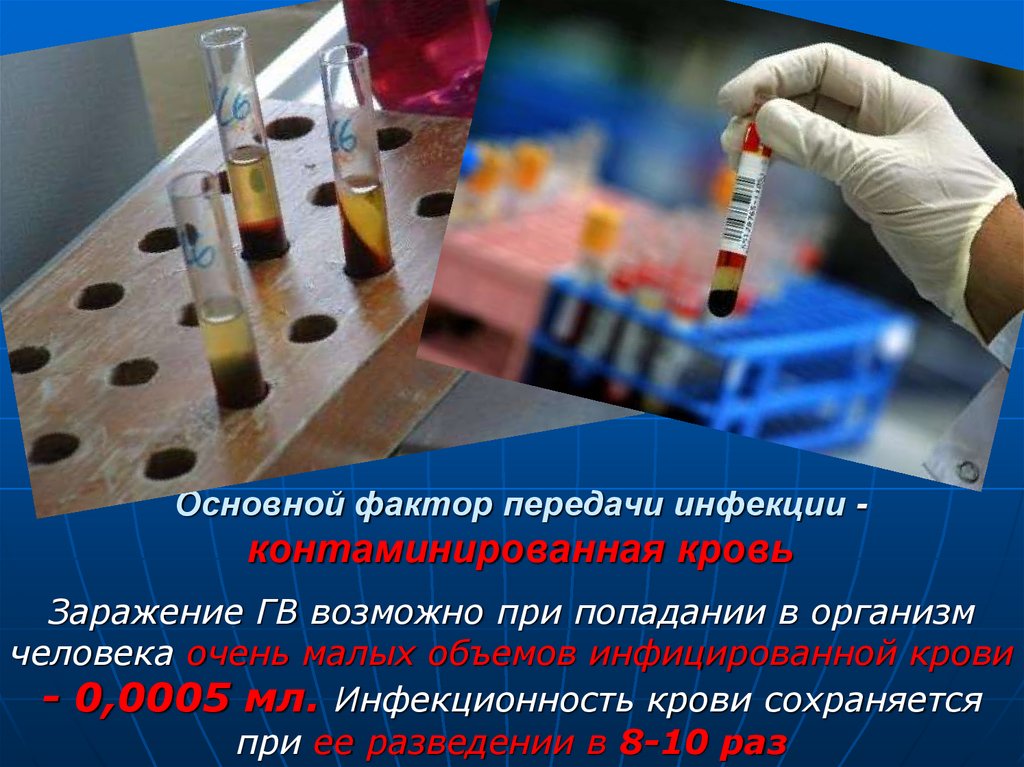

Факторы Риска ВПЧ: Визуальный Обзор и Информация